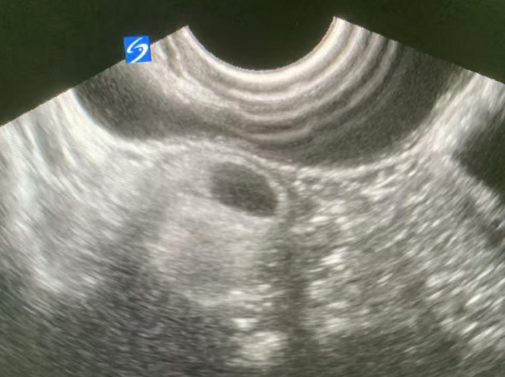

最重要的診斷工具是B超(超聲檢查)。有經(jīng)驗的醫(yī)生在B超圖像上能看到特征性的表現(xiàn),比如“面團(tuán)征”(團(tuán)狀的毛發(fā)和油脂)、“星花征”(漂浮的毛發(fā))、鈣化甚至牙齒和骨骼的強(qiáng)回聲光團(tuán)。CT或MRI(磁共振)可以更清晰地顯示腫瘤的結(jié)構(gòu)和與周圍組織的關(guān)系。